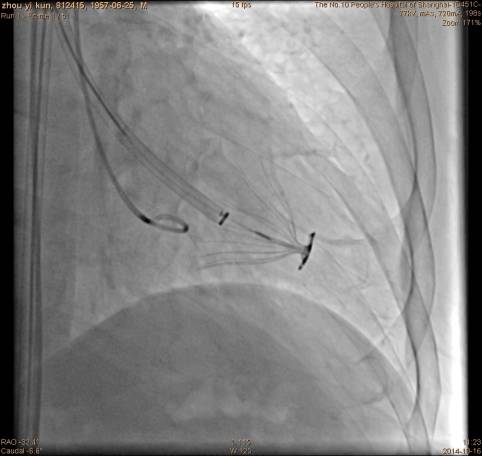

穿刺左侧股动脉,置入6F鞘管,行左心室造影;

手术过程左心室造影:

手术过程指引导管到达左心室:

手术过程隔离装置的脚到位:

手术过程充盈球囊:

手术过程装置到位后重复左心室造影: